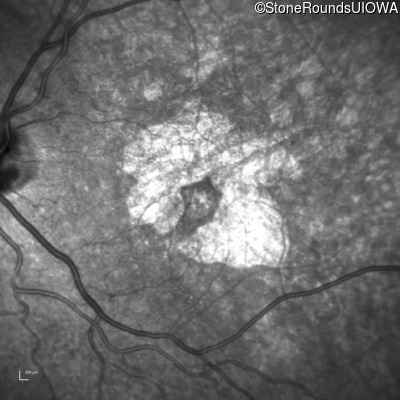

Infrared Fundus Photograph - Right - 20/32 +2

Exemplar